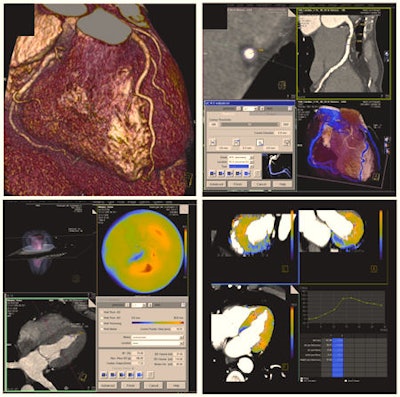

Here as well, CT presents a number of advantages. It has been used for more than 20 years to provide noninvasive examinations of the coronary arteries. Traditionally, CT's two main applications in cardiac imaging are calcium screening, which measures the amount of calcium in the arteries, and coronary CT angiography, which can reveal the degree of stenosis of the vessels.

CT angiography actually goes beyond risk assessment, and is typically carried out in a symptomatic patient with suspected coronary artery disease to exclude stenosis, for instance in a patient presenting with chest pain but not a typical angina. In such cases, the radiologist might be asked to perform a coronary CT angiography to prove or exclude the existence of stenosis and further characterize potential disease of the coronary arteries.

In addition, researchers have started to use CT to differentiate between types of coronary plaques. Plaques in the vessel wall not only consist of calcium, but also other tissues such as fibrotic, fibro-fatty and necrotic core tissues, all of which may have a predictive value for the patient. "Today, we would hardly make a clinical decision based on CT plaque imaging alone, but it is one of the important topics in cardiac CT research," Nikolaou said.

Current scientific studies have also been focusing on a more detailed analysis of the myocardium -- i.e., applying CT techniques instead of MRI to depict myocardial perfusion defects -- in order to gain time in the diagnostic process. "Patients are sometimes referred to nuclear medicine, or for an MRI scan for perfusion tests, when CT angiography results are inconclusive. We now try to get information on perfusion during the CT examination, by adding a CT perfusion scan to angiography," he said. "This would potentially enable us to get the whole picture in one examination and make a better clinical decision, based on the functional relevance of a given stenosis. Whether these rather new CT techniques will be used in everyday clinical routine is still not clear," he added.

Study results indicate that researchers will probably soon be able to find the perfusion defect caused by a stenosis with CT, the radiologist believes. "Depending on correct patient selection in accordance with cardiology, I think that we will, in a few years, start to use CT perfusion or CT dual imaging of the myocardium for the assessment of functional relevance of a coronary artery stenosis detected in CT angiography," he said.